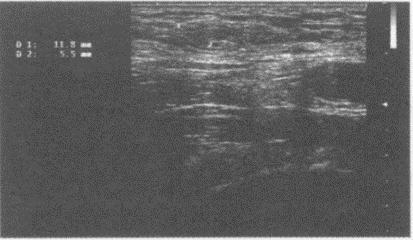

30、单项选择题

患者全身骨关节疼痛,有肾结石病史。行超声检查甲状腺,如图。最可能的诊断为()。

A.甲状腺腺瘤

B.甲状腺癌

C.甲状旁腺腺瘤

D.甲状腺囊肿

E.以上均不是